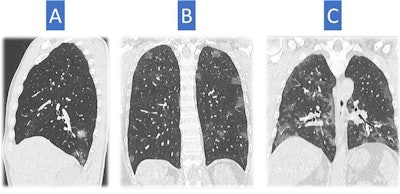

A frequently asked question is: Can you differentiate COVID-19 from other viral pneumonia? Sverzellati said the literature shows CT findings are entirely nonspecific and depict the most common form of pulmonary response to infections and other disorders: diffuse alveolar damage and organized pneumonia. He noted that in COVID-19, a number of nonspecific findings have been described, such as the crazy-paving, halo, and reverse atoll signs. However, there are other visible clues.

"Pay attention to the shape of abnormality. It's rounded, and this is more unusual compared to other types of infection and is not frequently seen in other disorders," he told viewers, adding that some atypical findings can help with differential diagnosis but that further investigation was needed to define typical signs and patterns.